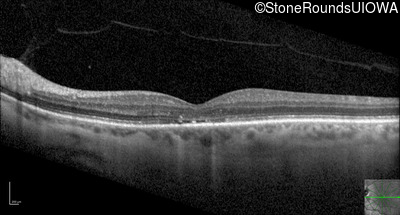

Optical Coherence Tomography - Left - 20/125

Exemplar / OCT Stack

OCT Stack